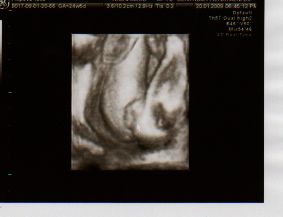

22.12.2008- velký UTZ v Centru Prenatální Diagnostiky na Veveří, vše je v pořádku, poprvé se mnou byl i manžel. Čekáme HOLČIČKU.

Pod stomeček jsme dostali i první pohyby